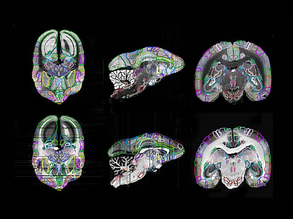

Learning from Primates